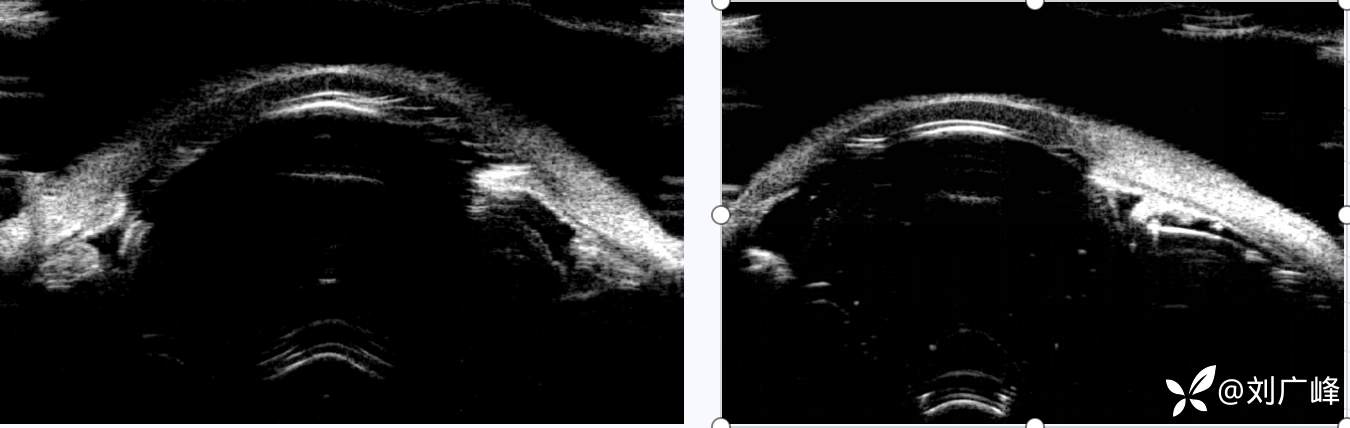

UBM

患者术后早期眼压不高,手术医师也在下方做了虹膜周切。但在复查时可以看到UBM上周边虹膜已经与角膜内皮相接触了,房角是关闭状态。 不知道大家还记得我以前处理急闭青缝合瞳孔的病例?其实我一直想找一个类似本病例的患者,来验证一些想法。